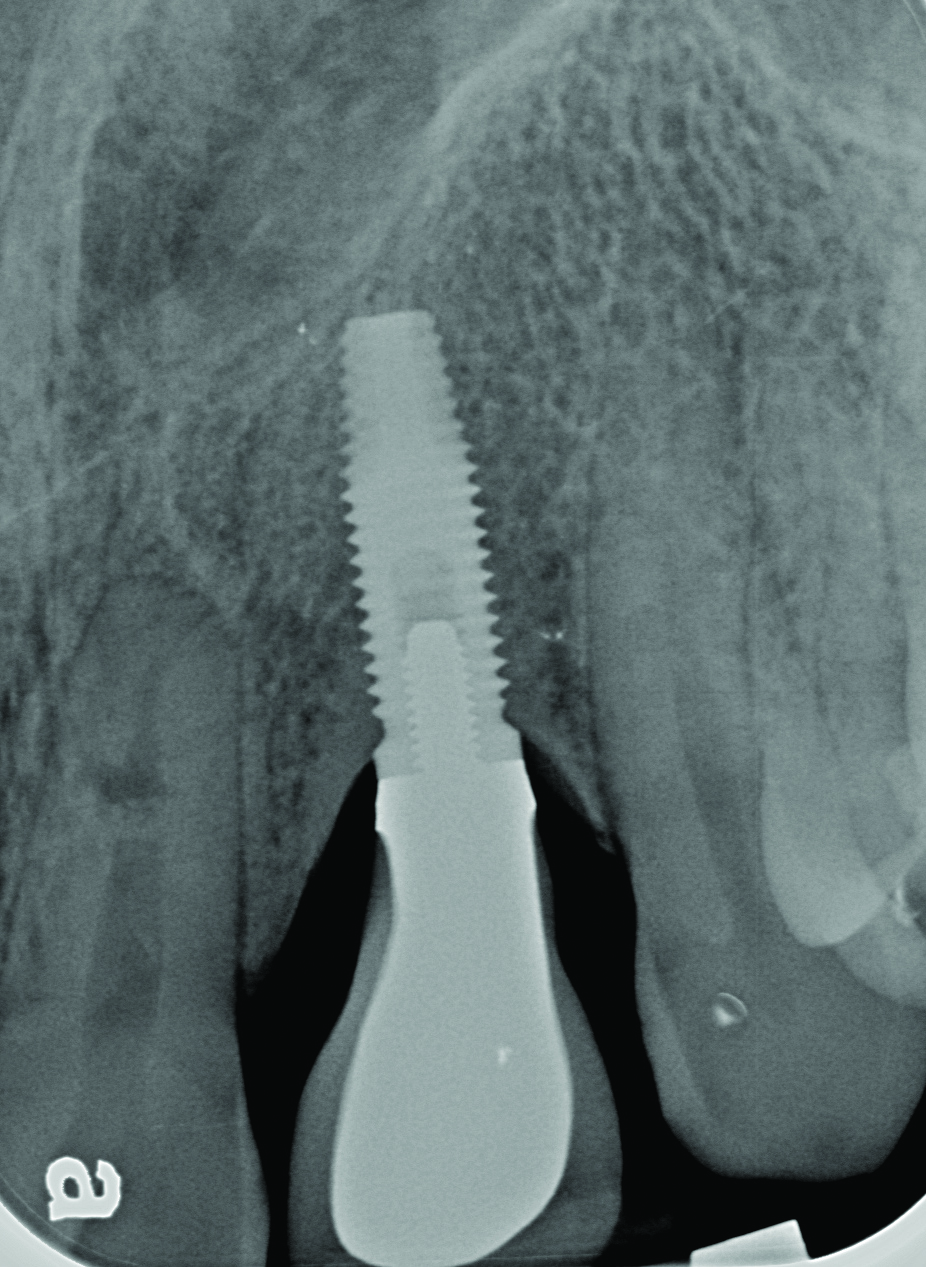

Radiograph of this same area. Note that there is no indication of bone loss and a long abutment collar. Hence, the diagnosis of peri-implant mucositis is given.

Figure 2